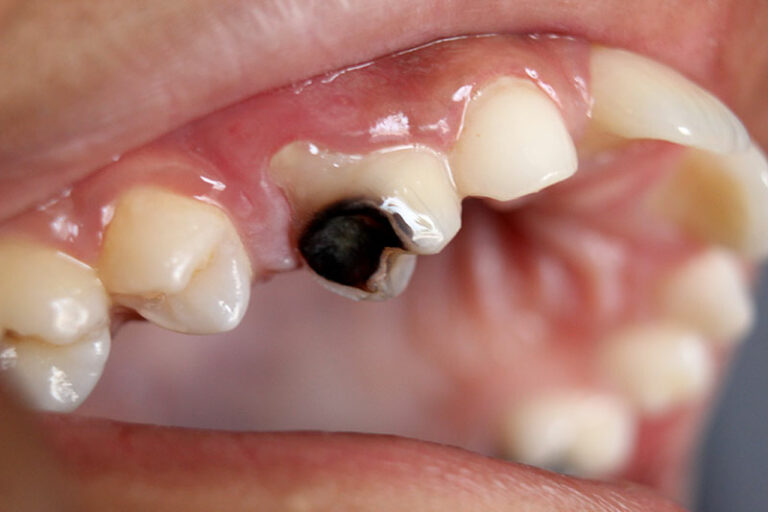

Thăm khám cấu trúc răng cần nhổ và kiểm tra sức khỏe răng miệng

Bác sĩ sẽ tiến hành thăm khám, chụp X – Quang để xác định hình dạng, vị trí và tình trạng xương xung quanh vị trí răng cần nhổ. Từ đó, bác sĩ ước tính mức độ khó của ca tiểu phẫu và hướng nhổ răng hợp lý nhất.